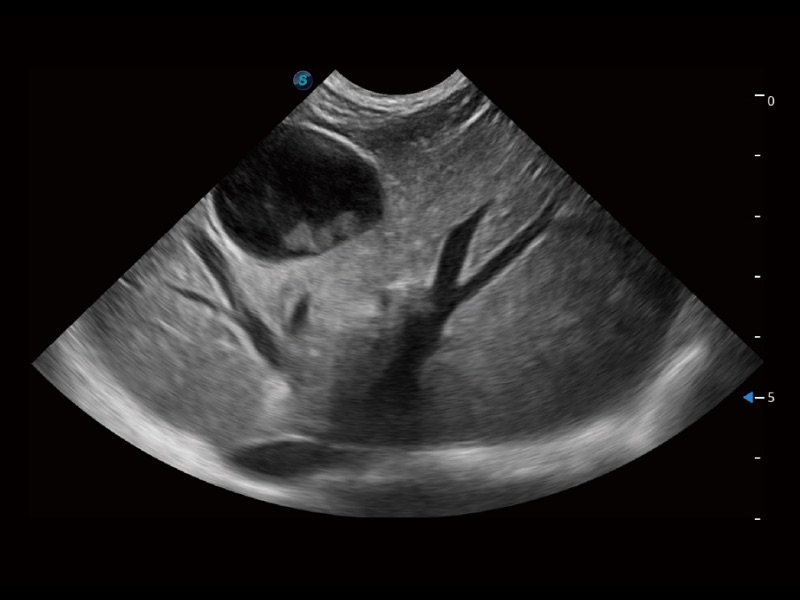

优异的基础图像

ProPet 70 全新的动物超声智能软件和丰富的探头群,为动物医生提供了高清晰度和精细分辨率的图像,无论在宠物、马科、畜牧还是实验室动物等应用中都可以轻松应对,为您的日常工作带来满意的体验。

(犬)四腔心

(犬)四腔心MQA